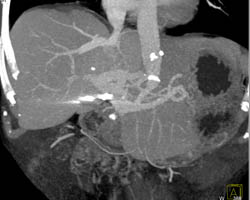

Budd-Chiari Syndrome